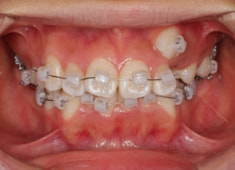

治療開始時

治療開始から11ヶ月後